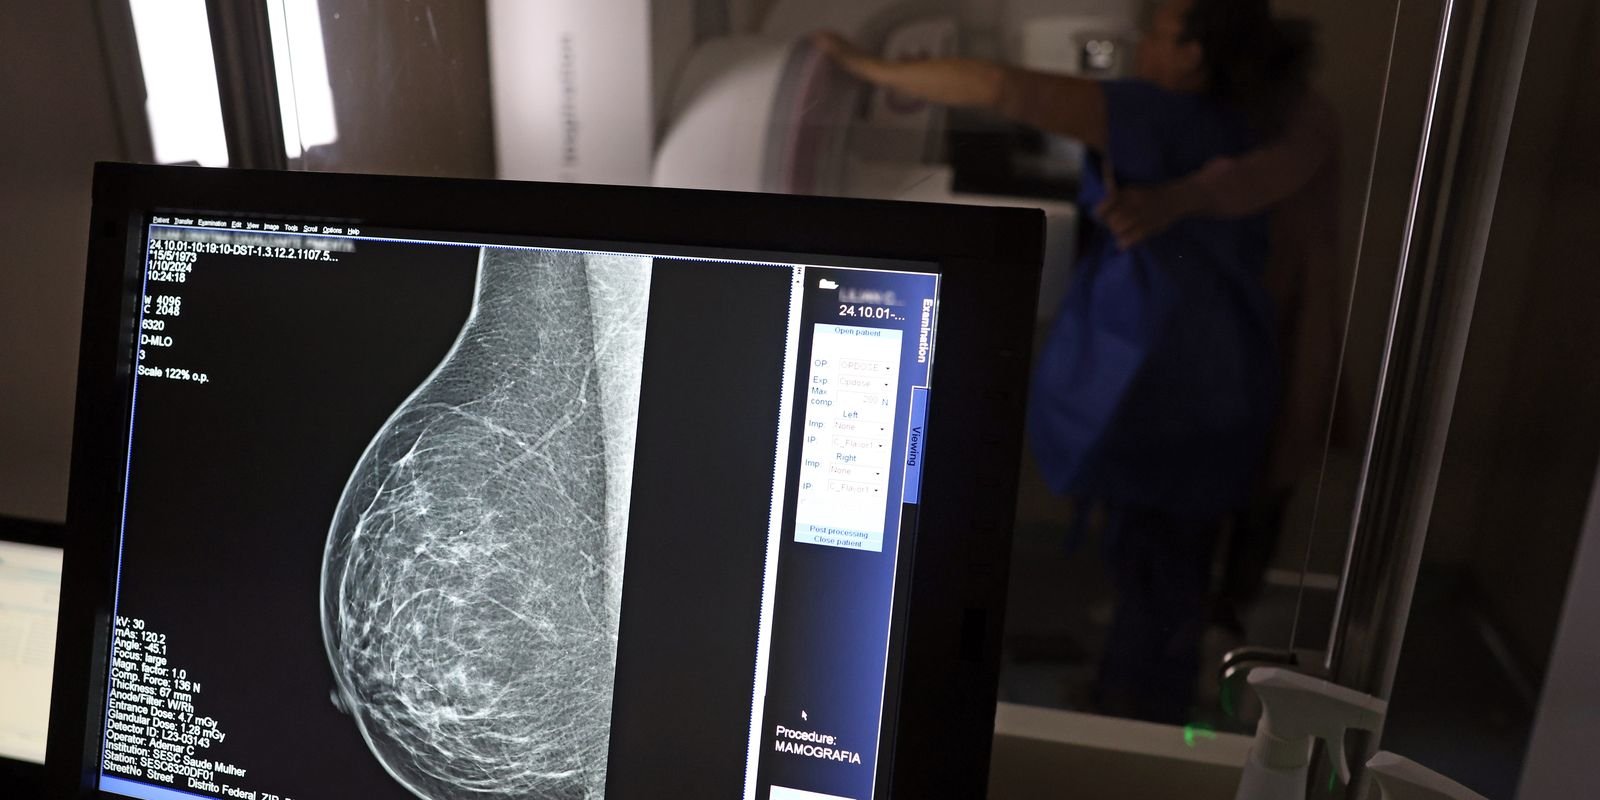

Ministério da Saúde passa a recomendar mamografia a partir dos 40 anos

O Ministério da Saúde passou a recomendar o acesso a mamografia, via Sistema Único de Saúde (SUS), para mulheres de 40 a 49 anos – mesmo que não haja sinais ou sintomas de câncer de mama. De acordo com a pasta, a faixa etária concentra 23% dos casos da doença, e a detecção precoce aumenta as chances de cura.

Até então, a orientação era que o exame fosse feito a partir dos 50 anos.

A medida faz parte de um conjunto de ações anunciadas nesta terça-feira (23) voltado para a melhoria do diagnóstico e da assistência. A recomendação para mulheres a partir dos 40 anos é que o exame seja feito sob demanda, em decisão conjunta com o profissional de saúde.